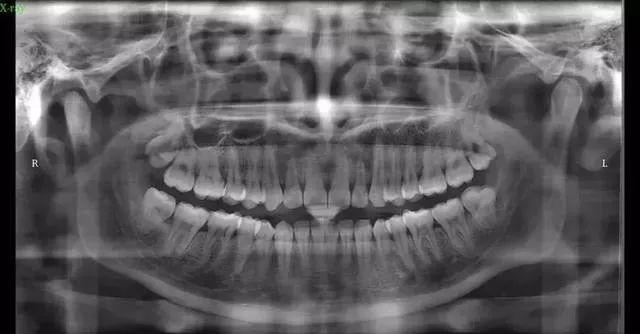

这阶段要跟医生沟通自己的诉求(例如想要把牙齿内收、想了解正畸后侧脸会不会有变化)、疑虑及价格等问题,也需要在这个阶段判断医生是否适合你。初步沟通后,拍口腔全景片,头颅侧位片、CT等,拍片的目的是为了看你的牙齿及骨骼发展方向等,以利于以后制定准确的矫正方法。